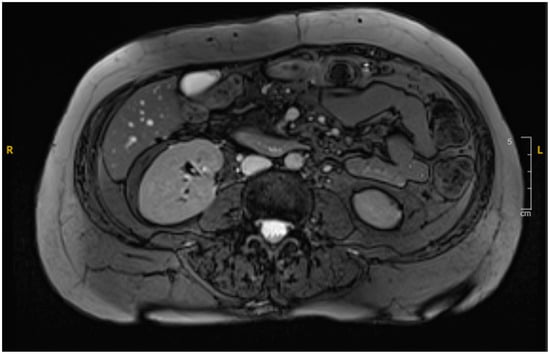

A CT scan of the abdomen revealed a heterogeneous lesion measuring 6.1 cm × 8.8 cm × 8.7 cm in the second portion of the duodenum with mild heterogeneous enhancement (Figure 1A). Given the imaging features, a duodenal malignancy was initially suspected. The attending physician decided to pursue further investigations to rule out malignancy, and the patient was admitted for a comprehensive evaluation to establish a definitive diagnosis. The following day, an MRI cholangiogram with contrast was performed, revealing a lesion measuring 7.8 cm × 5.8 cm, in the second and third parts of the duodenum. The lesion exhibited heterogeneity with a lack of enhancement, indicative of a duodenal hematoma (Figure 1B). The hematoma affected the duodenum and the head of the pancreas, likely causing extrinsic compression with mild bile duct dilation.

Figure 1. (A): Initial contrast-enhanced abdominal CT scan revealing duodenal hematoma measuring 8.8 cm in its widest diameter. (B): Follow-up MRI cholangiogram showing interval regression in size to 7.8 cm. Image quality was limited by motion artifact.